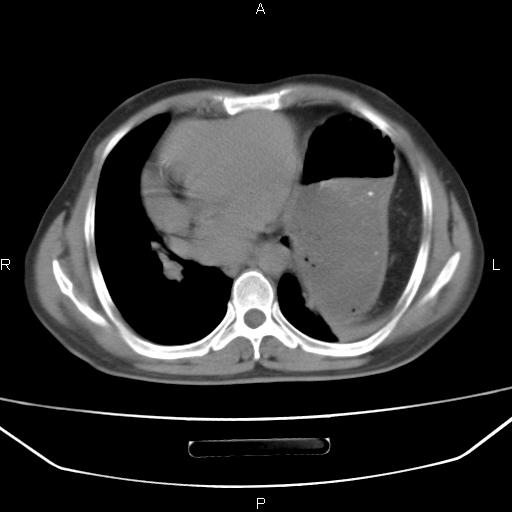

患者,男。50岁。近几日有咳嗽症状,无其他不适,既往病史无,考虑膈疝。请前辈们看看指导指导。

膈膨升,左下肺通气不良,膈肌好像还完整。

考虑左侧膈疝。

左侧膈疝。

符合隔膨升,膈肌较完整。